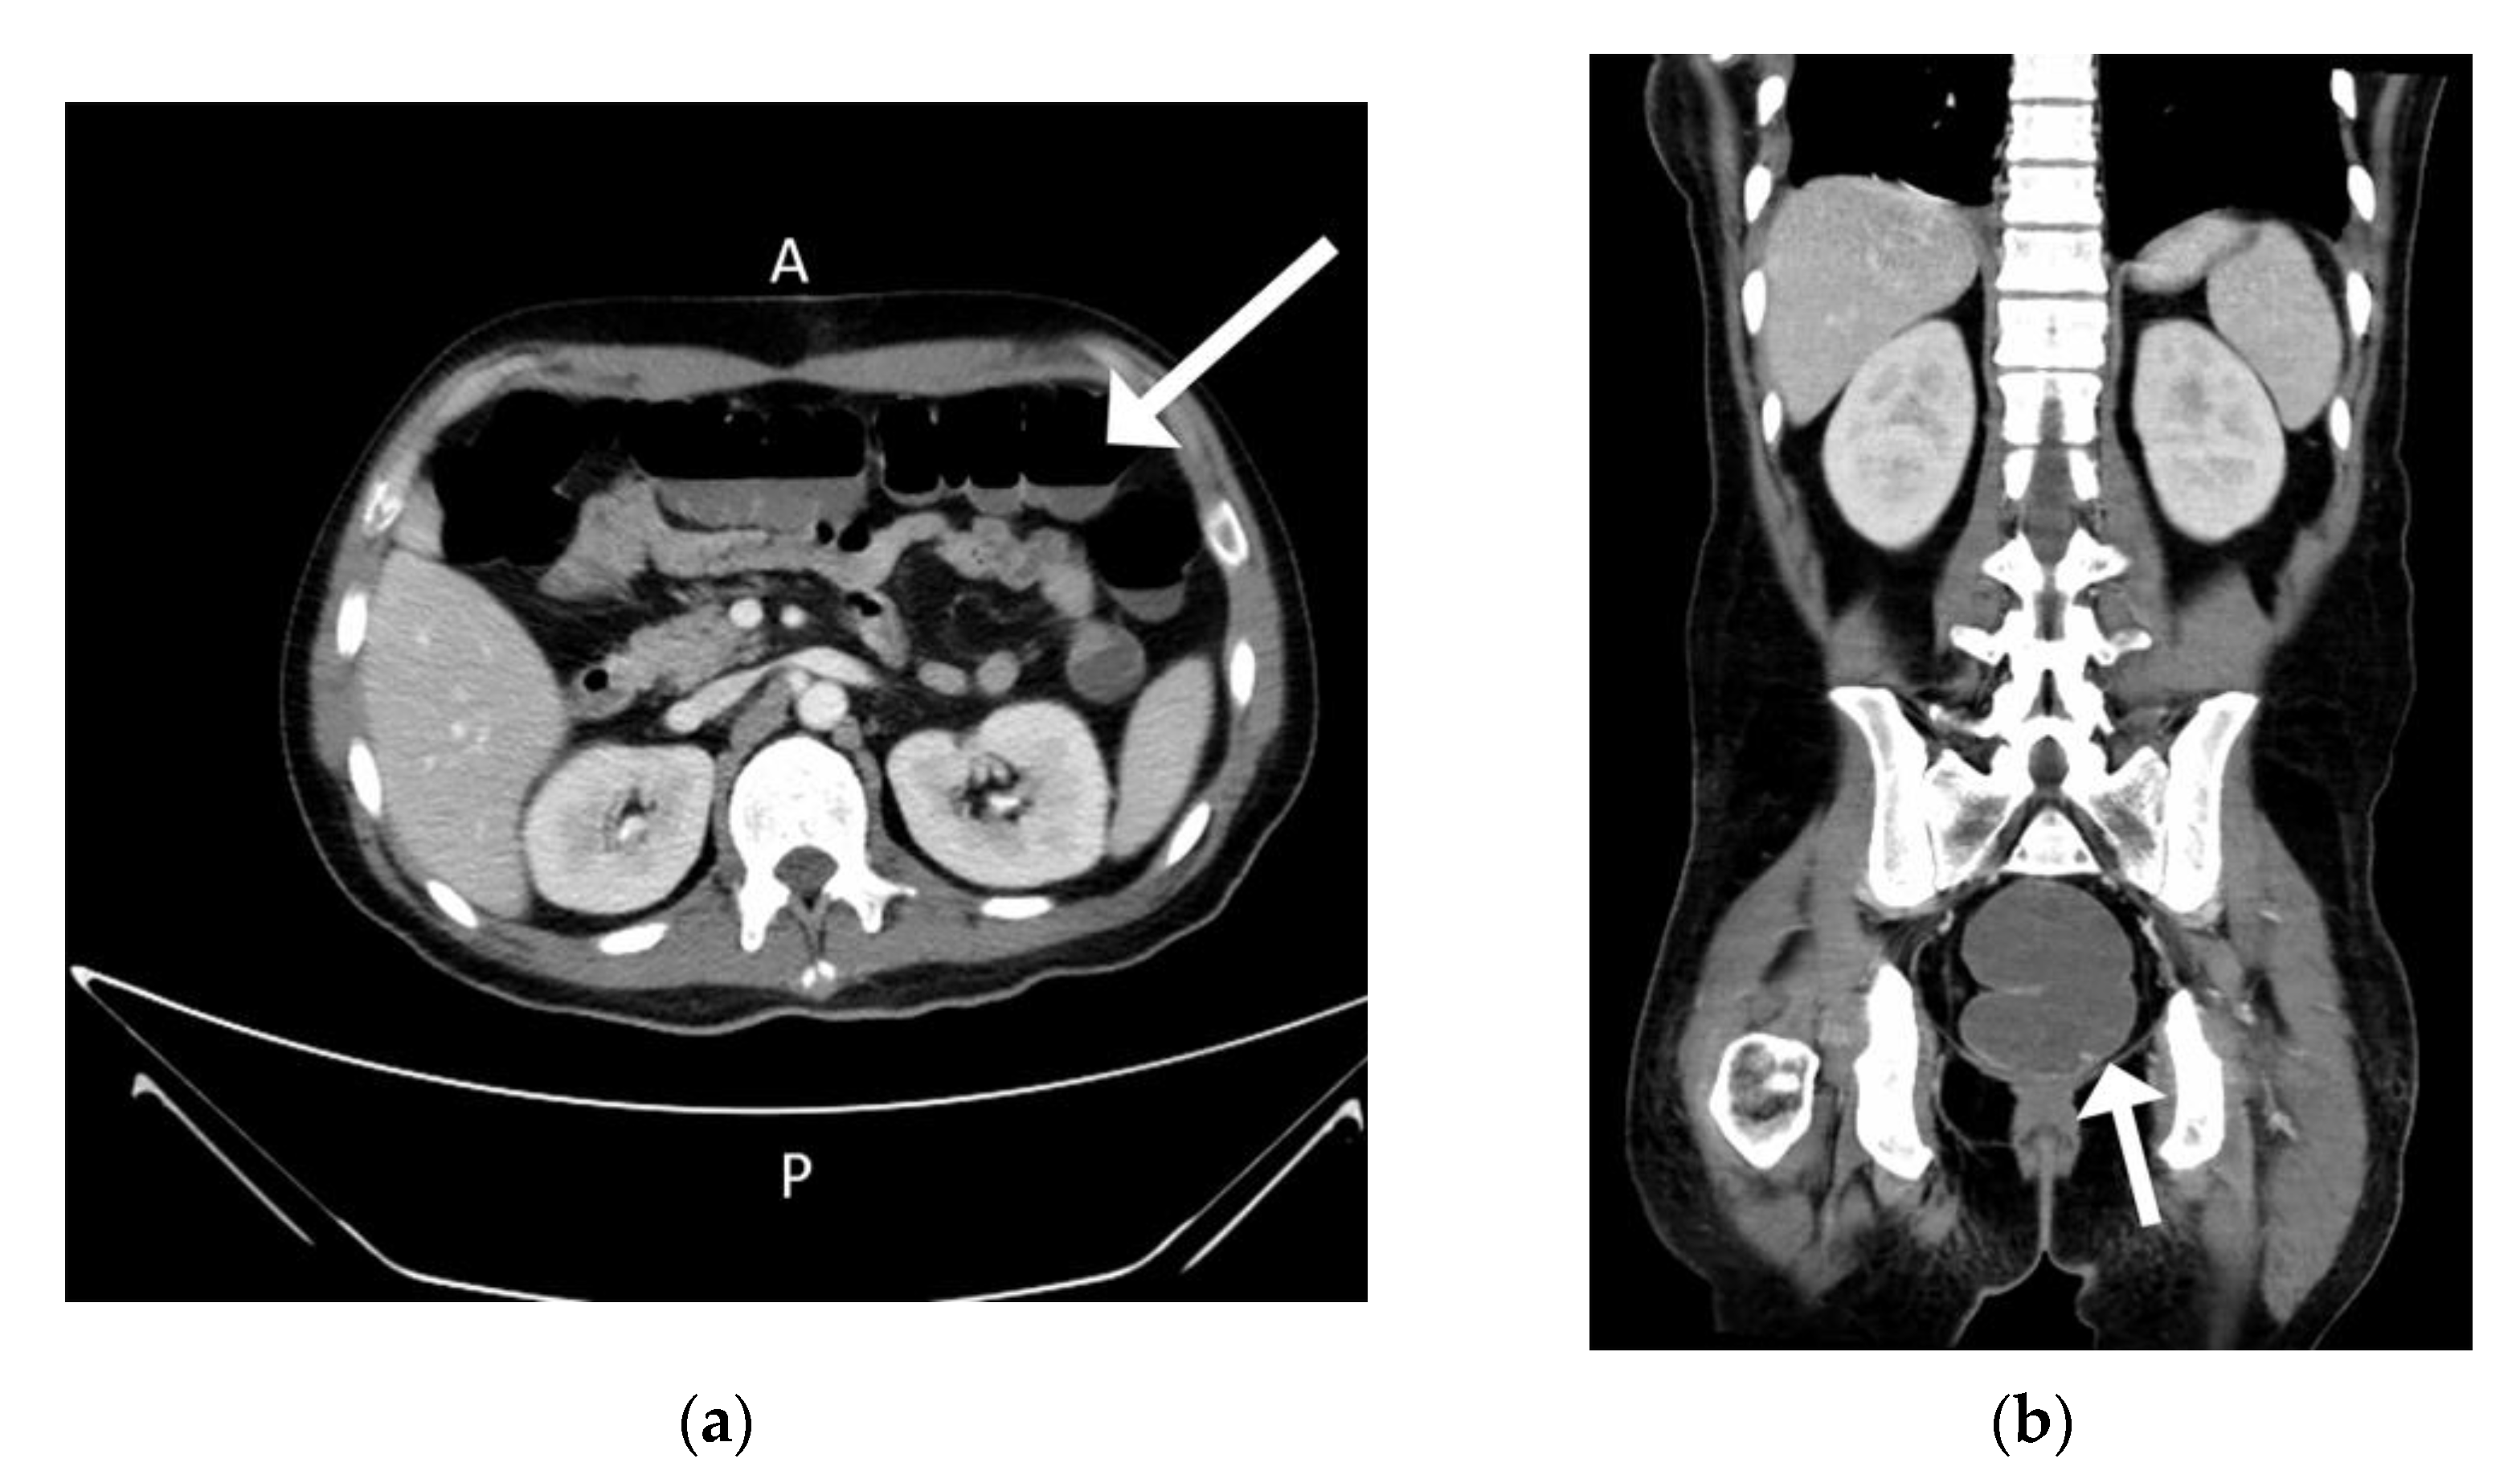

The patient was admitted to the division of rheumatology for suspected partially treated reactive arthritis. Blood tests revealed a white blood cell count of 11,330 cells/mm3, hemoglobin level of 9.0 g/dL, platelet count of 639,000 cells/mm3, creatinine level of 0.6 mg/dL, ALT level of 20 U/L, AST level of 124 U/L, CRP level of 24.27 mg/L, ferritin level of 3408 ng/mL and erythrocyte sedimentation rate of 117/h. Again, microbial examinations of sputum, blood, urine, and feces did not identify any pathogens. Blood sampling did not detect any autoantibodies. Cardiac echo–Doppler revealed no vegetation at the cardiac valves. Sonography of whole abdomen revealed coarsening echo-pattern which was suspected to be fatty liver disease related. Based on the examination protocol for fever with unknown origin [6], computed tomography scans with contrast of the chest showed a mass lesion in the anterior mediastinum and enlarged lymph nodes (Figure 3).

The serum carcinoembryonic antigen concentration was 0.92 ng/mL (normal range: 0.00–5.00 ng/mL), squamous cell carcinoma antigen level was 1.40 ng/mL (normal range: 0.00–2.10 ng/mL), alpha-fetoprotein level was 0.83 ng/mL (normal range for males: 0.00–10.00 ng/mL), carbohydrate antigen 19-9 level was 4.22 U/mL (normal range: 0.00–37.00 U/mL), and beta 2-microglobulin level was 2.72 mg/L (normal range: 1.00–2.40 mg/L). Video-assisted thoracoscopic surgery (VATs) tumor resection identified a mass measuring 7.2 cm × 5.6 cm × 4 cm in the anterior mediastinum (Figure 4) and two adjacent lymph nodes.

Figure 3. Computed Tomogram Scan with contrast at Chest revealed mass lesion over anterior mediastinum region.